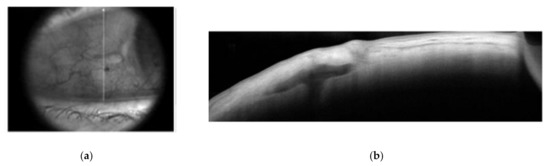

2.2.2. Sutureless Trans-Scleral Plugs Fixated Lens

2.3.2. Sutureless Trans-Scleral Plugs Fixated Lens Group (Group 2)